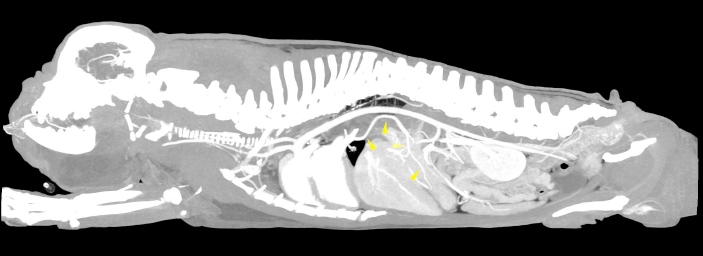

Fig. 1. Sagittal MIP view of the venous phase. The yellow arrowheads indicate the anomalous vessel connecting the portal system with the lobar vein of the caudal left pulmonary lobe.

A 5-year-old male French Bulldog of 13 kg was referred to our diagnostic center because of the presence of a voluminous swelling in correspondence of the intermandibular region, with a first suspect of a neoplastic lesion and less probably a severe sialocele. In the previous 2 weeks, the patient underwent a non-specified antimicrobial and anti-inflammatory therapy without significant improvements. The remote pathological anamnesis was silent. The anamnestic and clinical examination revealed depression, anorexia, severe breathing difficulty, abundant respiratory secretions and hyperthermia (39.8°C). Complete blood cell count (IDEXX ProCyte DxTM) indicated monocytosis (1.49 K/μl, range 0.16–1.12 K/μl), thrombocytopenia (64 K/μl, range 148–484 K/μl) and mild/moderate normocytic and normochromic non-regenerative anemia (RBC 4.53 M/μl, range 5.65–8.87 M/μl; HCT 28.0%, range 37.3%–61.7%, HGB 9.8 g/dl, range 13.1–20.5 g/dl), in first hypothesis indicating a chronic inflammatory disease. All biochemical parameters examined (IDEXX Catalyst OneTM), in particular alkaline phosphatase (ALP), gamma-glutamyl transferase (GGT), alanine aminotransferase (ALT), cholesterol, triglycerides, bilirubin, creatinine, urea and albumin were within normal limits, except for a mild increase in total proteins (10.0 g/dl, range 5.2–8.2 g/dl) and in globulin (7.7 g/dl, range 2.5–4.5 g/dl). The same day, the dog underwent a total-body CTA examination under general anesthesia, that was performed using a 16-slice scanner (GE Healthcare Optima CT520) with a slice thickness of 0.625 mm, 120 kW, 150 mA and a pitch < 1. The patient was positioned in sternal recumbency, and the image acquisition was carried out in the native scan phase and after about 40 seconds from the injection of 2 mg/kg iodinate contrast medium (Iopamiro, Iopamidolo 370 mgI/ml) followed by 1 mg/kg bolus of physiological solution (0.9% NaCl). Images were reformatted using bone and soft tissue algorithms. The CTA examination showed the presence of an anomalous vascular connection between the PV and the lobar vein of the caudal left pulmonary lobe. This anomalous vessel originated from the ventral aspect of the PV, cranially to the portal entering of the gastroduodenal vein. The vase went caudo-ventrally along the small gastric curvature, and subsequently dorso-cranially towards the esophageal hiatus, receiving two branches of the left gastric vein. At the hiatus, the shunt rotated dorsally around and in contact with the cardias, from the median line to the left side of the dog. Afterwards, the vessel entered the lobar vein of the caudal left pulmonary lobe, 1.1 cm before its entry into the left atrium (Figs. 1 and 2). The porto-pulmonary shunt showed an almost constant diameter, starting from 2.0 mm at its origin in correspondence of the PV, increasing to 2.6 mm at the level of the esophageal hiatus and 3.4 mm before entering the left lobar pulmonary vein. The diameter of the PV was 6.8 mm at the porta hepatis, while it was 7.8 mm before the origin of the anomalous vase. Neither hepatic lesions nor intraparenchymal portal vascular texture anomalies were observed, and the hepatic volume was within normal limits. No other shunts, varices, peritoneal effusion or CTA-perceived cardiac abnormalities were detected. No nephromegaly, based on renal length-to-aorta diameter (Hoey et al., 2016), was observed. The dog also underwent an echocardiographic and an abdominal ultrasound examination, performed by an experienced radiologist, without evidences of functional or morphological abnormalities. The final clinical diagnosis consisted of a severe infected sialocele sustained by Fusobacterium necrophorum isolated by cultural examination and the presence of the porto-pulmonary shunt was interpreted as an incidental finding. The patient died the following day because of respiratory failure and the owner did not allow the necropsy.